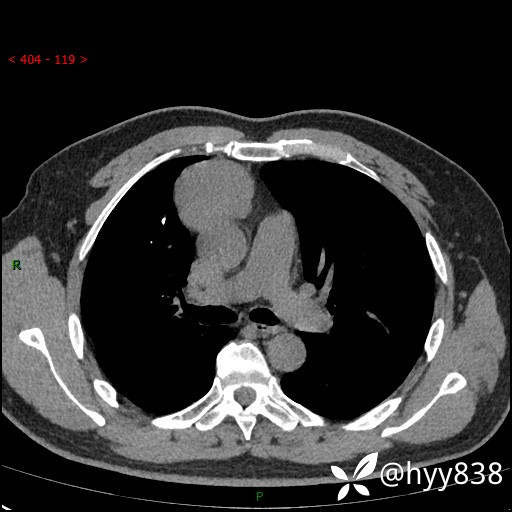

动脉期+静脉期

各期CT值